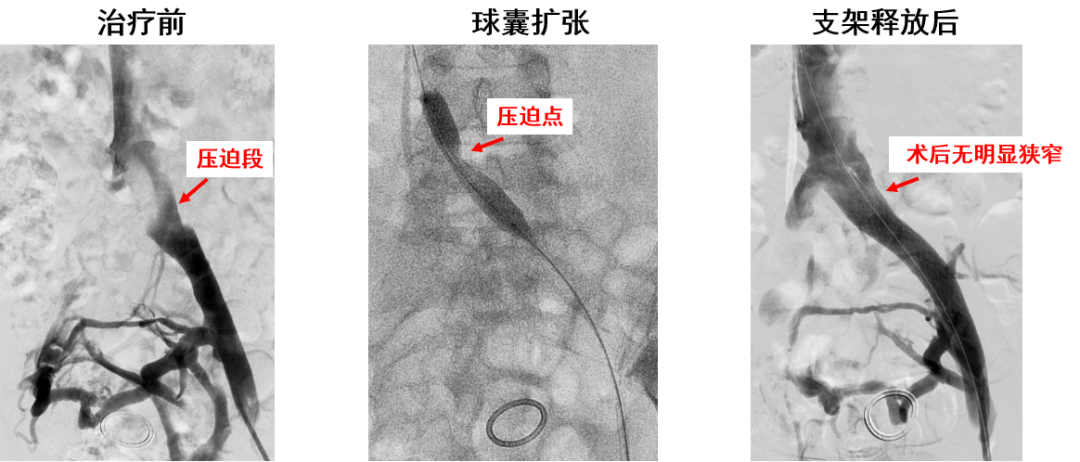

产品A:病例一

产品A:病例二

产品B:病例一

产品B:病例二(DVT合并Cockett综合征)

产品C:病例二(髂总静脉远端受压)